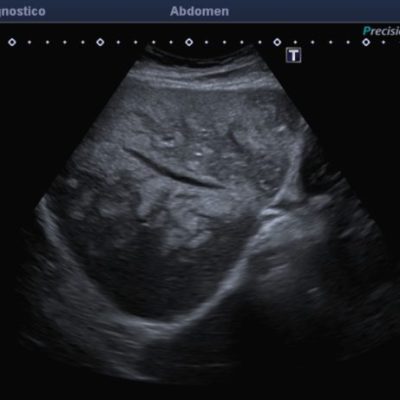

El médico de referencia le indica nueva ecografía de control, donde se observan múltiples y extensas lesiones focales hepáticas hiperecogénicas, redondeadas y confluentes, las cuales predominan en adyacencia a venas supra hepáticas, sin condicionar efecto de masa y sin alteración de la superficie hepática(fig. 1 y 2). Ante la valoración con Doppler color no presenta patrón de flujo peri ni intralesional y respeta el calibre de las venas supra hepáticas(fig. 3 y 4). Dada las características ecográficas se sospecha esteatosis focal multinodular confluente como principal diagnóstico presuntivo, siendo los diagnósticos diferenciales patologías de naturaleza infecciosa, tumoral o metastásica.